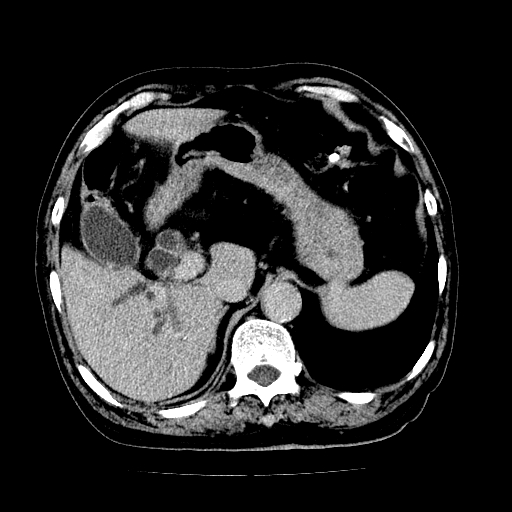

男,71岁,皮肤黄染四天。

肝内外胆管及胆总管上段扩张,考虑为梗阻所致,建议mrcp检查。

考虑胆总管癌并肝内外胆管扩张。

支持考虑胆总管癌并肝内外胆管扩张。 局部应薄扫。心包钙化。

胰腺上端胆总管内见软组织影,强化不明显,结合临床,还是考虑低位梗阻性黄疸,胆总管癌可能性大